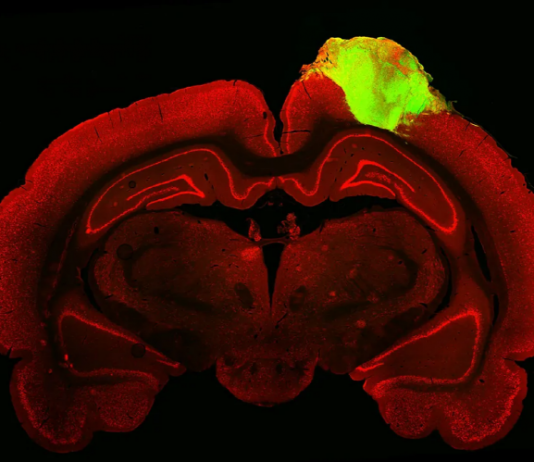

실험실에서 키운 '뇌 오르가노이드(미니 뇌)'로 살아있는 생쥐의 뇌 손상 부위를 복구하는 데 성공했다. 이는 미래에 인간의 뇌를 복구할 수 있는 가능성을 시사한다.펜실베이니아대 페렐만의대 신경외과 조교수인 한샤오 이삭 첸(Han-Chiao Isaac Chen) 연구팀은 인간 줄기세포에서 성장시킨 미니 뇌를 쥐 시각피질(visual cortex)에 이식하는 데 성공했다.연구 결과(논문명: Structural and functional integration of human...